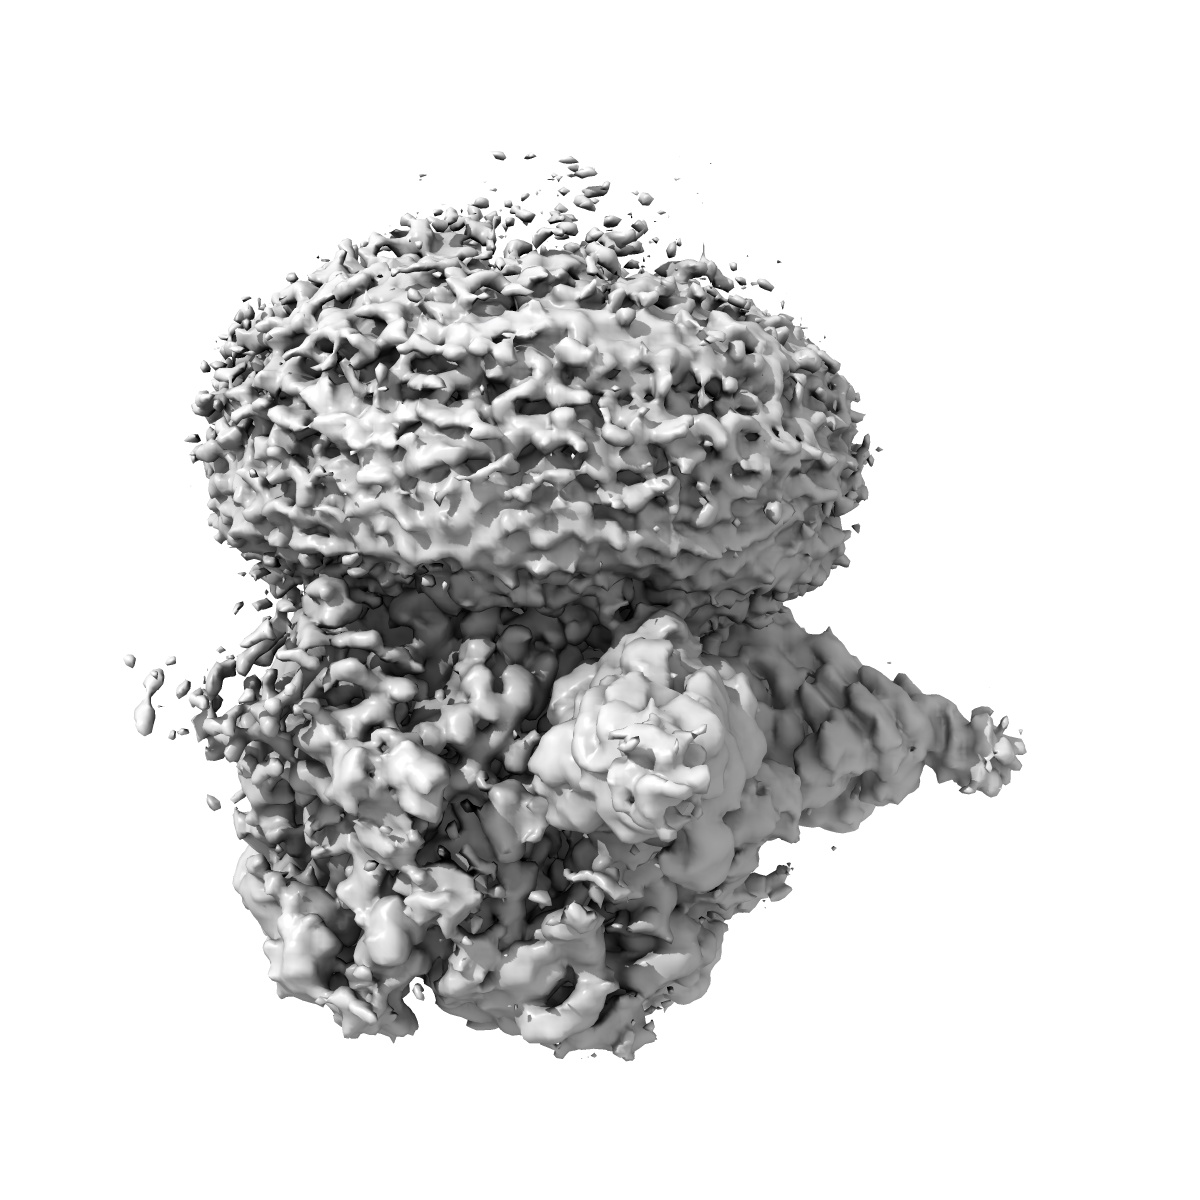

Cryo-EM structure of human full-length extrasynaptic alpha4beta3delta GABA(A)R in complex with GABA, histamine and nanobody Nb25 in a pre-open/closed state

Single-particle2.9 Å

Sample: Human full-length extrasynaptic alpha4beta3delta GABA(A)R in complex with histamine and nanobody Nb25